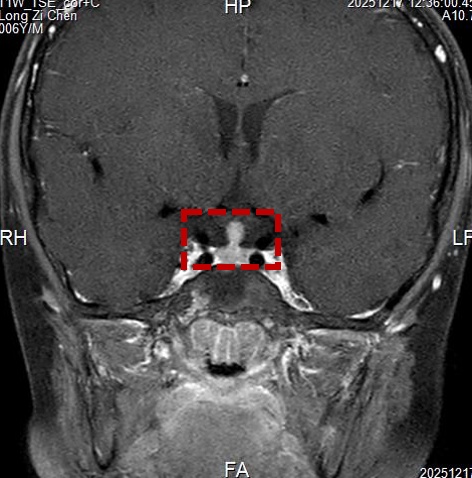

为了明确诊断,必须获取病变的垂体柄组织进行病理分析。但儿童脑部手术风险极高,如何在精准取到活检组织的同时,最大限度地保护孩子的大脑功能、减少创伤?张晨冉主任团队给出了一个精妙的答案:眉弓锁孔入路手术。

该手术切口并不在头顶部,而是巧妙地隐藏在孩子的右侧眉毛里,长度仅约4厘米左右。医生通过这个“钥匙孔”大小的骨窗,借助显微镜和神经内镜的辅助,精准地抵达脑深部的鞍区。术中,医生在显微镜下清晰地分辨出视神经、颈内动脉等重要结构,并在增粗的垂体柄上小心翼翼地钳取了数块组织送检。术中冰冻病理结果提示“朗格汉斯细胞组织细胞增生症待定”。由于这类肿瘤对化疗敏感,为了避免过度切除对患儿造成不必要的神经功能损伤,手术团队果断决定,在明确病理后终止切除,将主要任务锁定在“精准活检”。整个手术过程顺利,出血极少。术后,小晨被安全送回监护室病房。

术后病理结果给出了最终答案:结合形态学及BRAF基因V600E突变检测,病变明确诊断为 “朗格汉斯细胞组织细胞增生症(LCH)”。